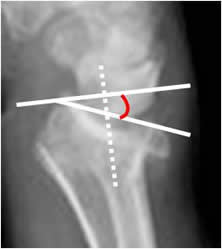

Angulo escafolunado:

Tiene una amplitud normal entre 30º y 60º. El eje del escafoides se traza uniendo los bordes anteriores superior e inferior y el del lunado, por una línea perpendicular a la unión de sus polos distales.

Fig 51. Angulo escafolunado.

A: Rx lateral de muñeca. Intersección entre los ejes de los huesos escafoides y lunado.